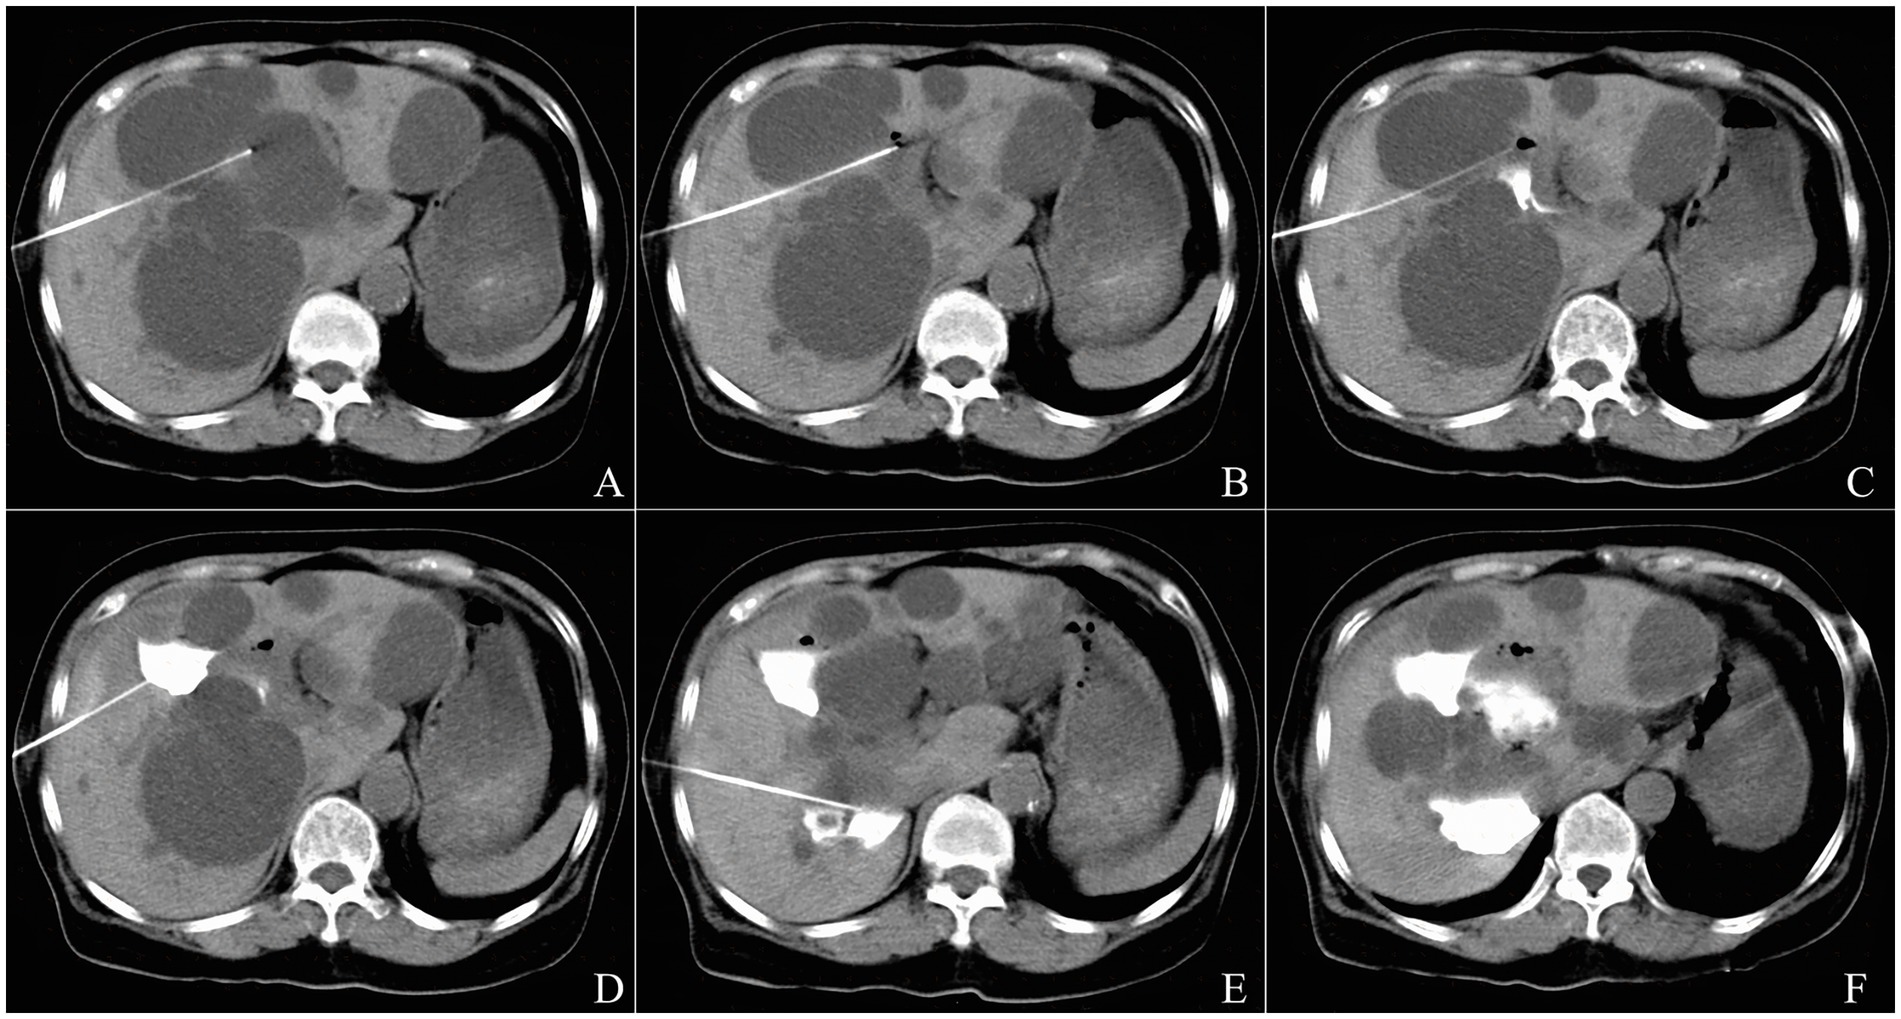

Regarding imaging-based treatment responses, the cysts refilled partially in the initial stage after sclerotherapy and decreased gradually in size throughout the entire follow-up period, without significantly changes since 12-months after the procedure (Figure 4). At the 6-month follow-up, CR was observed in 11 cysts (11.4%), and near-CR in 20 cysts (20.8%), and PR (%) in 62 cysts (64.6%), and NR in 3 cysts (3.1%). At 12-month follow-up, 14 cysts (14.6%) achieved CR, 67 cysts (69.8%) achieved near-CR, and 15 cysts (15.6%) achieved PR. At 24- and 36-month follow-up, 14 cysts (14.6%) achieved CR, 68 cysts (70.8%) achieved near-CR, and 14 cysts (14.6%) achieved PR.

CT scans (A–C) and ultrasound images (D–E) showing progressive cyst volume reduction over 36 months following bleomycin sclerotherapy.

Figure 4. A typical example of the imaging-based treatment response after CT-guided percutaneous aspiration and bleomycin sclerotherapy in a 69-year-old man with a simple left renal cyst. Preprocedural CT scan shows an initial cyst volume of 554.4 mL (12.6 cm × 8.8 cm × 10.0 cm in size) (A). At 6-month follow-up, CT shows a cyst volume of 34.3 mL (4.9 cm × 3.5 cm × 4.0 cm in size) and the volume reduction rate (VRR) of 93.8% (B). At 12-month follow-up, CT shows a cyst volume of 1.7 mL (20.0 mm × 13.3 mm × 13.0 mm in size) and the volume reduction rate (VRR) of 99.7% (C). At 24-month follow-up, US shows a cyst volume of 1.2 mL (15.6 mm × 12.4 mm × 13.0 mm in size) and the volume reduction rate (VRR) of 99.8% (D). At 36-month follow-up, US shows a cyst volume of 0.7 mL (12.6 mm × 9.8 mm × 12.0 mm in size) and the volume reduction rate (VRR) of 99.9% (E).